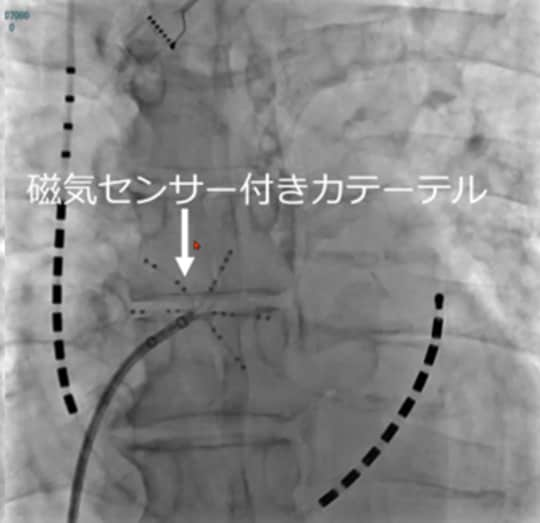

[図表2]が、患者さんの心臓のレントゲン写真です。心臓にカテーテルが入っていることがおわかりいただけるでしょうか。

このカテーテルには磁気センサーがあり、ベッドの真下には磁場発生装置があります。つまり、磁場発生装置により磁気センサー付きカテーテルを動かすことで、空間的な位置を正確に認識することができるのです。